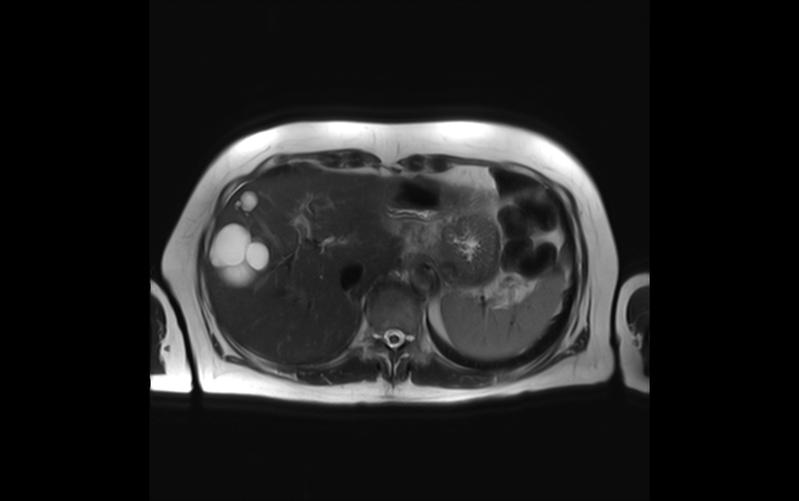

Bessere Bilder von der Leber

Es gibt einige Gründe, warum Ärztinnen und Ärzte möglichst gute Bilder von der Leber brauchen. Zum Beispiel streuen viele Tumorarten Metastasen in die Leber,…

Viszeralchirurgen und Radiologen setzen bei Lebertumor-OP erstmals intraoperatives MRT der Leber ein

Durch den Einsatz des intraoperativen MRT (ioMRT) lässt sich Narbengewebe in der Leber besser von vitalem Tumorgewebe unterscheiden als mit herkömmlichen…